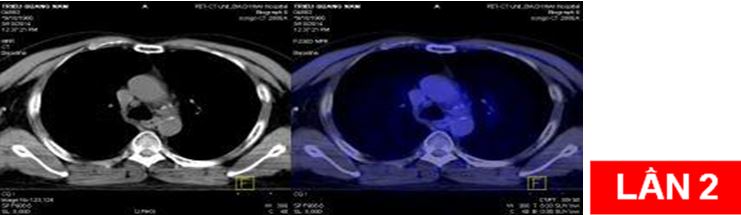

Bệnh nhân:chụp PET/CT lần 2 đánh giá sau 6 chu kỳ hóa chất (có đối chiếu với lần chụp trước khi điều trị).

Sau điều trị: hết u và hạch di căn